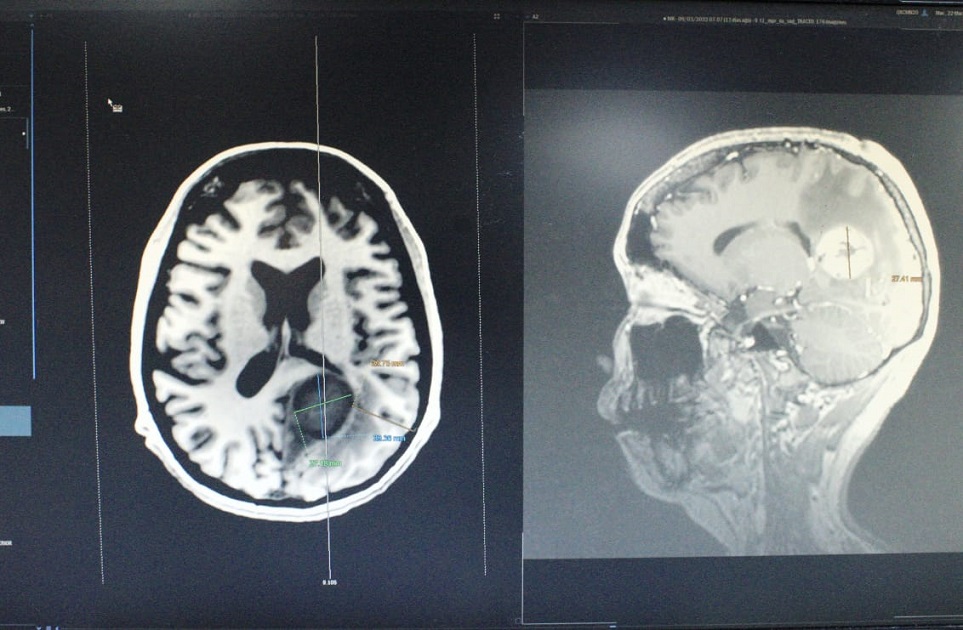

“Le realizamos una tomografía y observamos una lesión dentro del cerebro. En estudio de resonancia magnética identificamos una lesión nodular con bordes bien definidos y con gran edema cerebral”, explicó.

Posteriormente, se programó la neurocirugía, un procedimiento de alta especialidad en el que utilizamos tecnologías médicas como microscopio quirúrgico, neuronavegador y ultrasonido transquirúrgico, con el propósito de realizar un acceso hacia el tumor localizado en la parte profunda del cerebro, señaló.